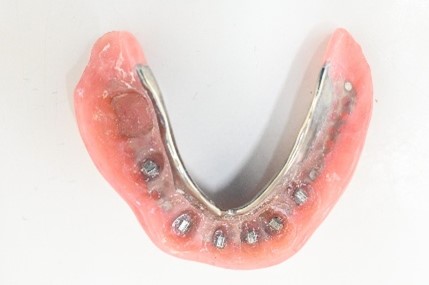

【マグネット式総入れ歯】

上顎

下顎